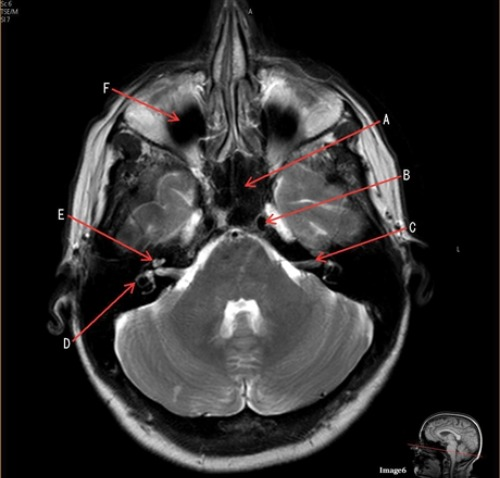

Letter C in Image 6 is pointing to:

A. 7th cranial nerve

Letter B in Image 6 is pointing to:

D. Internal carotid artery

Letter D in Image 6 is pointing to:

D. Semicircular canal

Letter E in Image 6 is pointing to:

B. Cochlea

Letter F in Image 6 is pointing to:

A. Maxillary sinus

Letter A in Image 6 is pointing to:

B. Sphenoid sinus

Image 6 is an example of a ____ weighted sequence acquired in the _____ imaging plane.

C. T2; Axial